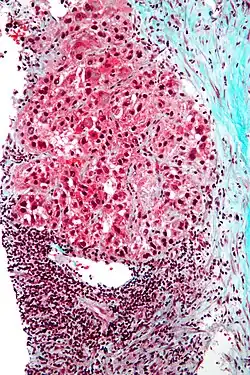

![]() Carcinoma hepatocelular en un individuo que dio positivo por hepatitis C. Muestra de autopsia. | ||